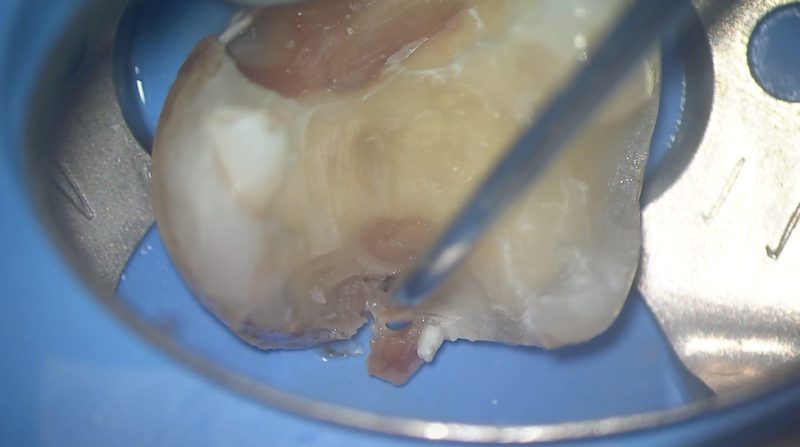

修復物の近心側を削除していくと、大きな虫歯が出てきました。

修復物の遠心側を削除すると、ここも大きな虫歯がありました。

虫歯が大きいです。